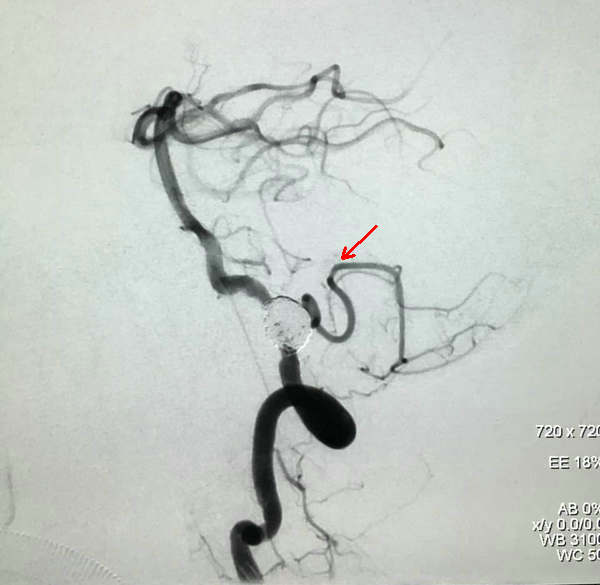

栓塞完成后造影,PICA保留完好(红箭头所示)

颅内段椎动脉夹层动脉瘤是颅内动脉瘤中较特殊的一种类型,其病死率高,治疗难度大,一直是神经外科治疗的一大难题。随着神经介入治疗的迅速发展,特别是微弹簧圈栓塞与支架技术的联合应用,使得介入治疗成为了首选方案。但由于颅内段椎动脉解剖的特殊性,尤其是动脉瘤与小脑后下动脉(PICA)的关系,为了保证PICA的通畅,需要使用不同的治疗策略。此病例的完美治疗,王师傅的顺利出院代表着郑州大学五附院神经外科一病区在介入治疗动脉瘤方面迈上了更高的台阶。